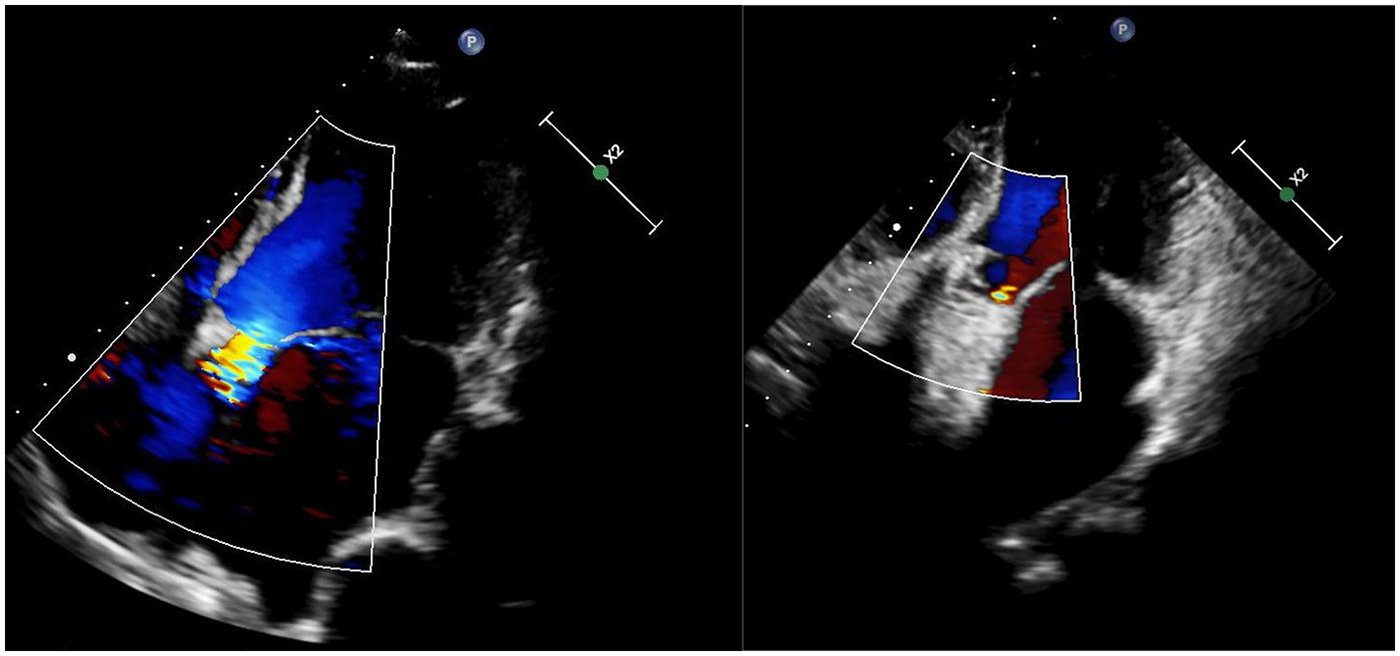

A 38-year-old male with Marfan syndrome underwent Bentall + Sun's surgery for aortic dissection. Three months later, he was readmitted with exertional dyspnea. Echocardiography confirmed a paravalvular leak with high-velocity flow across the defect into the right atrium via a surgically created shunt, resulting in heart failure. The patient declined reoperation. Multimodal imaging—including echocardiography (Figure 1, Supplementary Video S1) and computed tomography (Figure 2, Supplementary Video S2)—was used to plan transcatheter PVL closure.

Figure 1

Echocardiograms before (left) and after (right) the procedure.

Post-procedural echocardiography (Figure 1, Supplementary Video S3) showed minimal residual leak. Follow-up CT (Figure 2) demonstrated significant reduction in pseudoaneurysm size. No complications—such as hemolysis, device migration, new PVL, or recurrent heart failure—were observed. The outcome was satisfactory.